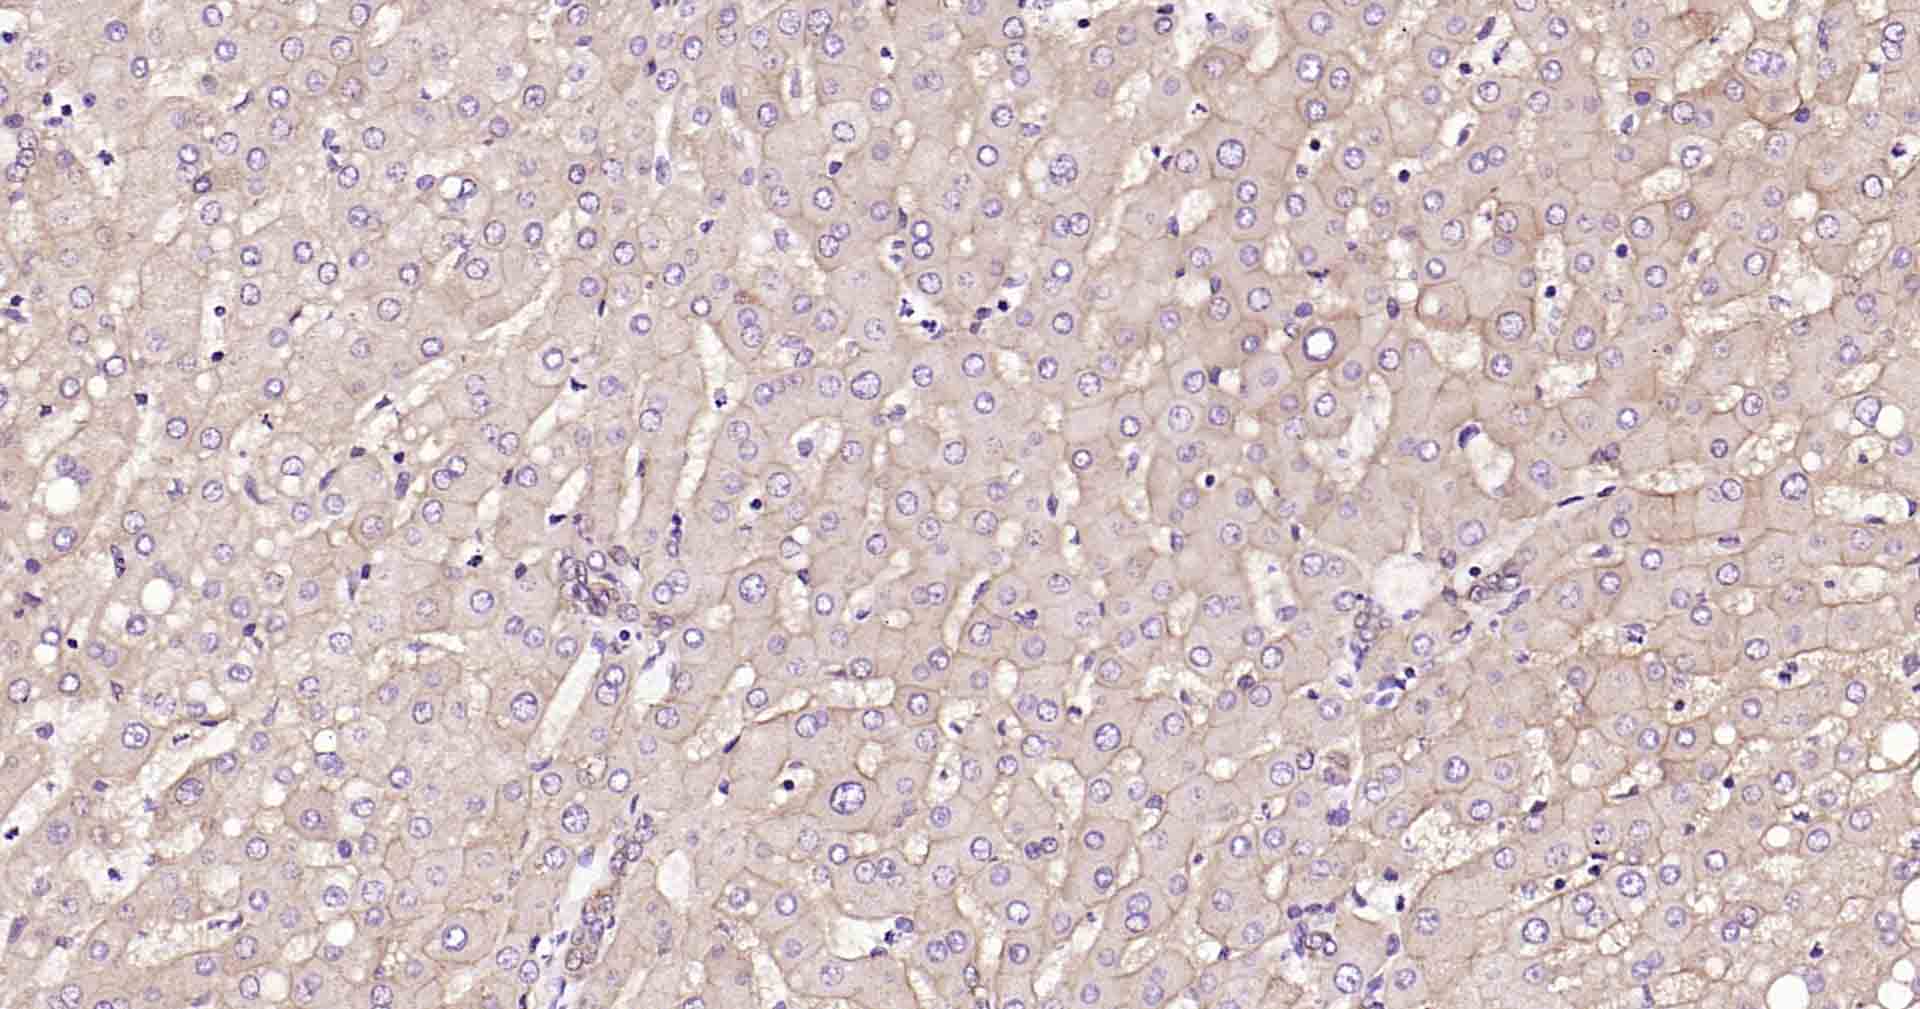

Paraformaldehyde-fixed, paraffin embedded Human Liver; Antigen retrieval by boiling in sodium citrate buffer (pH6.0) for 15 min; Antibody incubation with ATP1B1 Monoclonal Antibody, Unconjugated(bsm-61065R) at 1:100 overnight at 4°C, followed by conjugation to the SP Kit (Rabbit, SP-0023) and DAB (C-0010) staining.

Paraformaldehyde-fixed, paraffin embedded Human Heart; Antigen retrieval by boiling in sodium citrate buffer (pH6.0) for 15 min; Antibody incubation with ATP1B1 Monoclonal Antibody, Unconjugated(bsm-61065R) at 1:100 overnight at 4°C, followed by conjugation to the SP Kit (Rabbit, SP-0023) and DAB (C-0010) staining.

Paraformaldehyde-fixed, paraffin embedded Rat Heart; Antigen retrieval by boiling in sodium citrate buffer (pH6.0) for 15 min; Antibody incubation with ATP1B1 Monoclonal Antibody, Unconjugated(bsm-61065R) at 1:100 overnight at 4°C, followed by conjugation to the SP Kit (Rabbit, SP-0023) and DAB (C-0010) staining.

Paraformaldehyde-fixed, paraffin embedded Mouse Heart; Antigen retrieval by boiling in sodium citrate buffer (pH6.0) for 15 min; Antibody incubation with ATP1B1 Monoclonal Antibody, Unconjugated(bsm-61065R) at 1:100 overnight at 4°C, followed by conjugation to the SP Kit (Rabbit, SP-0023) and DAB (C-0010) staining.